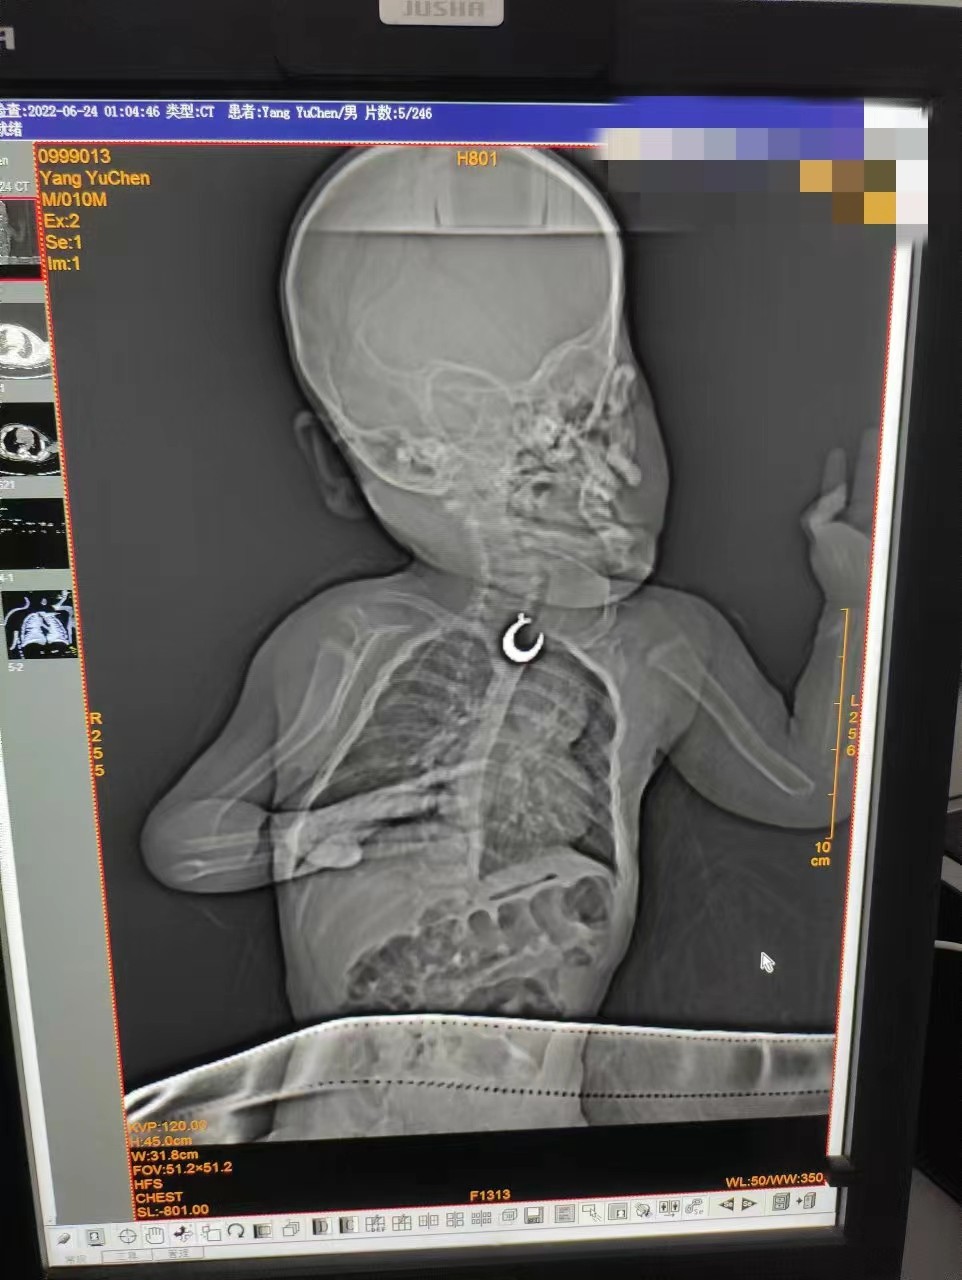

10月龄男童,身高75cm,体重11kg,因误食金属吊坠10小时入院,入院后无流涎、呕吐,吞咽不适感,口唇无青紫,无咳嗽、喘鸣、呼吸困难。生命体征:呼吸28次/分,血压91/55mmhg,脉搏114次/分,体温36.4℃。

2.影像学检查: